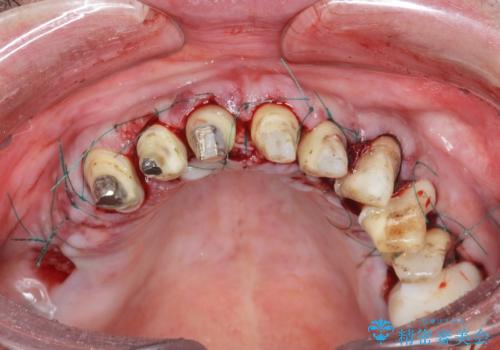

- 前医で行った前歯セラミック形態の改善、常に腫れぼったく歯ブラシの際に出血のある前歯部の治療を希望され来院されました。

前医により、前歯は歯ぐきの奥深くまで形成されこのままの状態でセラミックをやりかえたとしても歯ぐきの腫れの改善は難しい状況です。

歯周外科を行い歯と歯槽骨・歯肉の関係を是正することで歯ぐきの状態を改善し、将来に亘り安定した歯周環境の維持を期待できるセラミック治療を実践します。